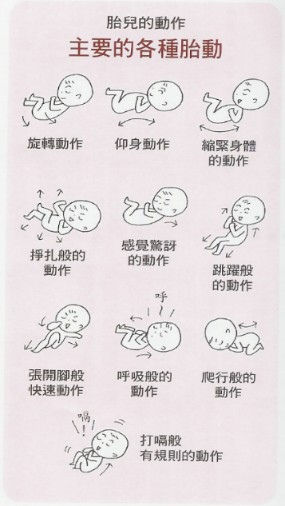

胎动有快有慢 时强时弱 可能是胎宝宝在肚子里做这件事呢 胎儿

胎動 時寶寶在肚裡是這樣 醫影片告訴你一天可動幾百次 Ettoday健康雲 Ettoday新聞雲

有頻率的胎動 愛淘生活